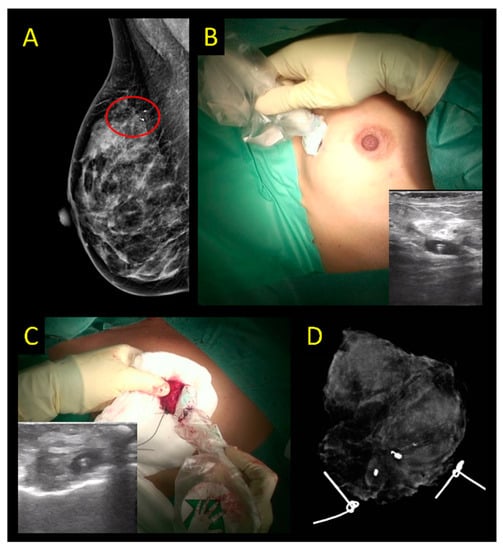

2.2. Radioactive Localization

- Monti, S.; Galimberti, V.; Trifiro, G.; De Cicco, C.; Peradze, N.; Brenelli, F.; Fernandez-Rodriguez, J.; Rotmensz, N.; Latronico, A.; Berrettini, A.; et al. Occult breast lesion localization plus sentinel node biopsy (SNOLL): Experience with 959 patients at the European Institute of Oncology. Ann. Surg. Oncol. 2007, 14, 2928–2931. [Google Scholar] [CrossRef] [PubMed]

- Moreno, M.; Wiltgen, J.E.; Bodanese, B.; Schmitt, R.L.; Gutfilen, B.; da Fonseca, L.M. Radioguided breast surgery for occult lesion localization—Correlation between two methods. J. Exp. Clin. Cancer Res. 2008, 27, 29. [Google Scholar] [CrossRef] [PubMed]

- Medina-Franco, H.; Abarca-Perez, L.; Ulloa-Gomez, J.L.; Romero, C. Radioguided localization of clinically occult breast lesions (ROLL): A pilot study. Breast J. 2007, 13, 401–405. [Google Scholar] [CrossRef]